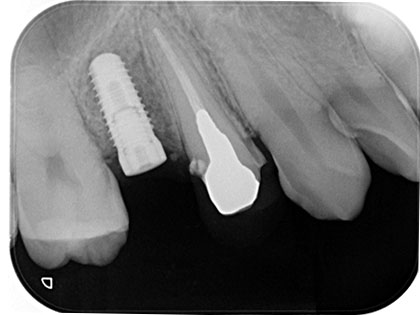

• 治療中のレントゲン写真がこちら

• インプラント治療中1